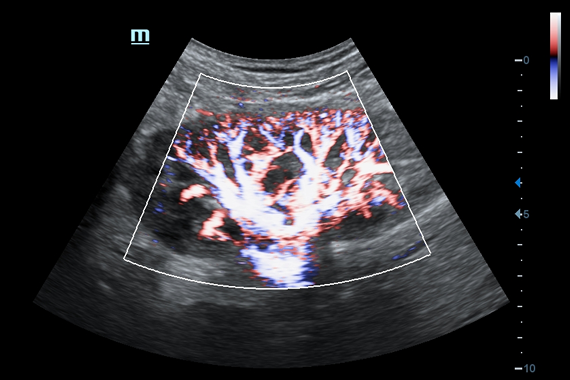

• HR Flow - режим отображения кровотока с высоким временным и пространственным разрешением для точной и однородной визуализации сосудов, в том числе самых мелких.

Энергетический допплер:

Да

Цветовой допплер:

• HR Flow - режим отображения кровотока с высоким временным и пространственным разрешением для точной и однородной визуализации сосудов, в том числе самых мелких